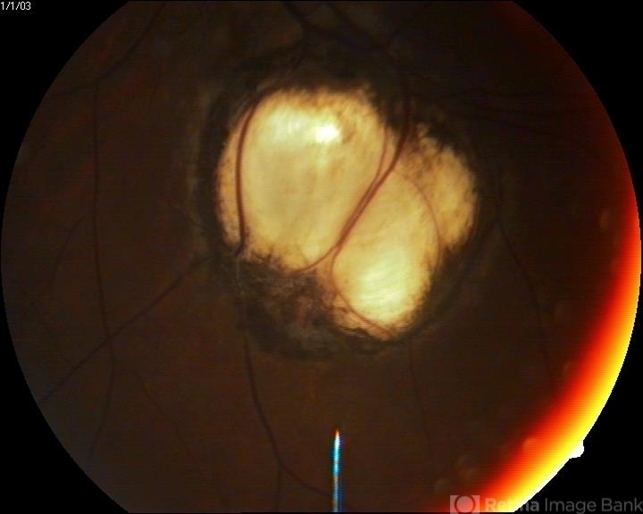

- 15-year-male patient presented with for routine check up was found to have colobomas not involving disc and macula.